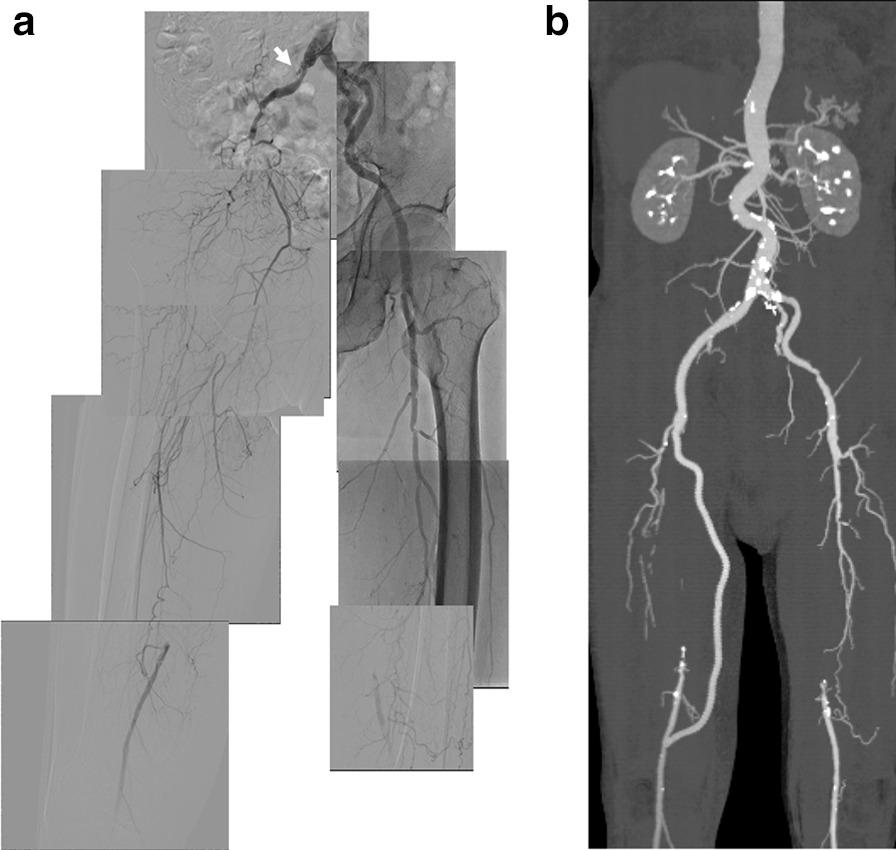

A 72-year-old Japanese man was admitted with acute limb ischemia due to failed aortofemoral and femoropopliteal bypass grafts. Endovascular treatment with balloon angioplasty, thrombectomy, and stent implantation in the long chronic total occlusion from the right common iliac artery to the superficial femoral artery did not result in efficient flow due to thrombus transfer from a failed aortofemoral bypass graft. However, a rescue femorofemoral bypass (the left femoral to the right deep femoral artery) improved his symptoms, and implanted in-stent flow was gradually recovered. Lower extremity angiography performed 5 months later confirmed the patency of the iliofemoral in-stent flow. However, the femorofemoral bypass graft was unfortunately occluded due to the progression of left external iliac artery stenosis. The patency of the iliofemoral in-stent flow was confirmed at 1 year by ultrasonography.

一名72岁的日本男性因主-股动脉和股-腘动脉旁路移植失败导致急性肢体缺血入院。对从右髂总动脉至股浅动脉的长段慢性完全闭塞病变进行球囊血管成形术、血栓切除术和支架植入的血管腔内治疗,因主-股动脉旁路移植失败导致的血栓转移,未能实现有效血流。然而,一次抢救性股-股动脉旁路移植术(从左股动脉至右股深动脉)改善了他的症状,支架内植入后的血流逐渐恢复。5个月后进行的下肢血管造影证实了髂股动脉支架内血流的通畅。然而,不幸的是,由于左髂外动脉狭窄进展,股-股动脉旁路移植血管闭塞。1年后通过超声检查证实了髂股动脉支架内血流的通畅。